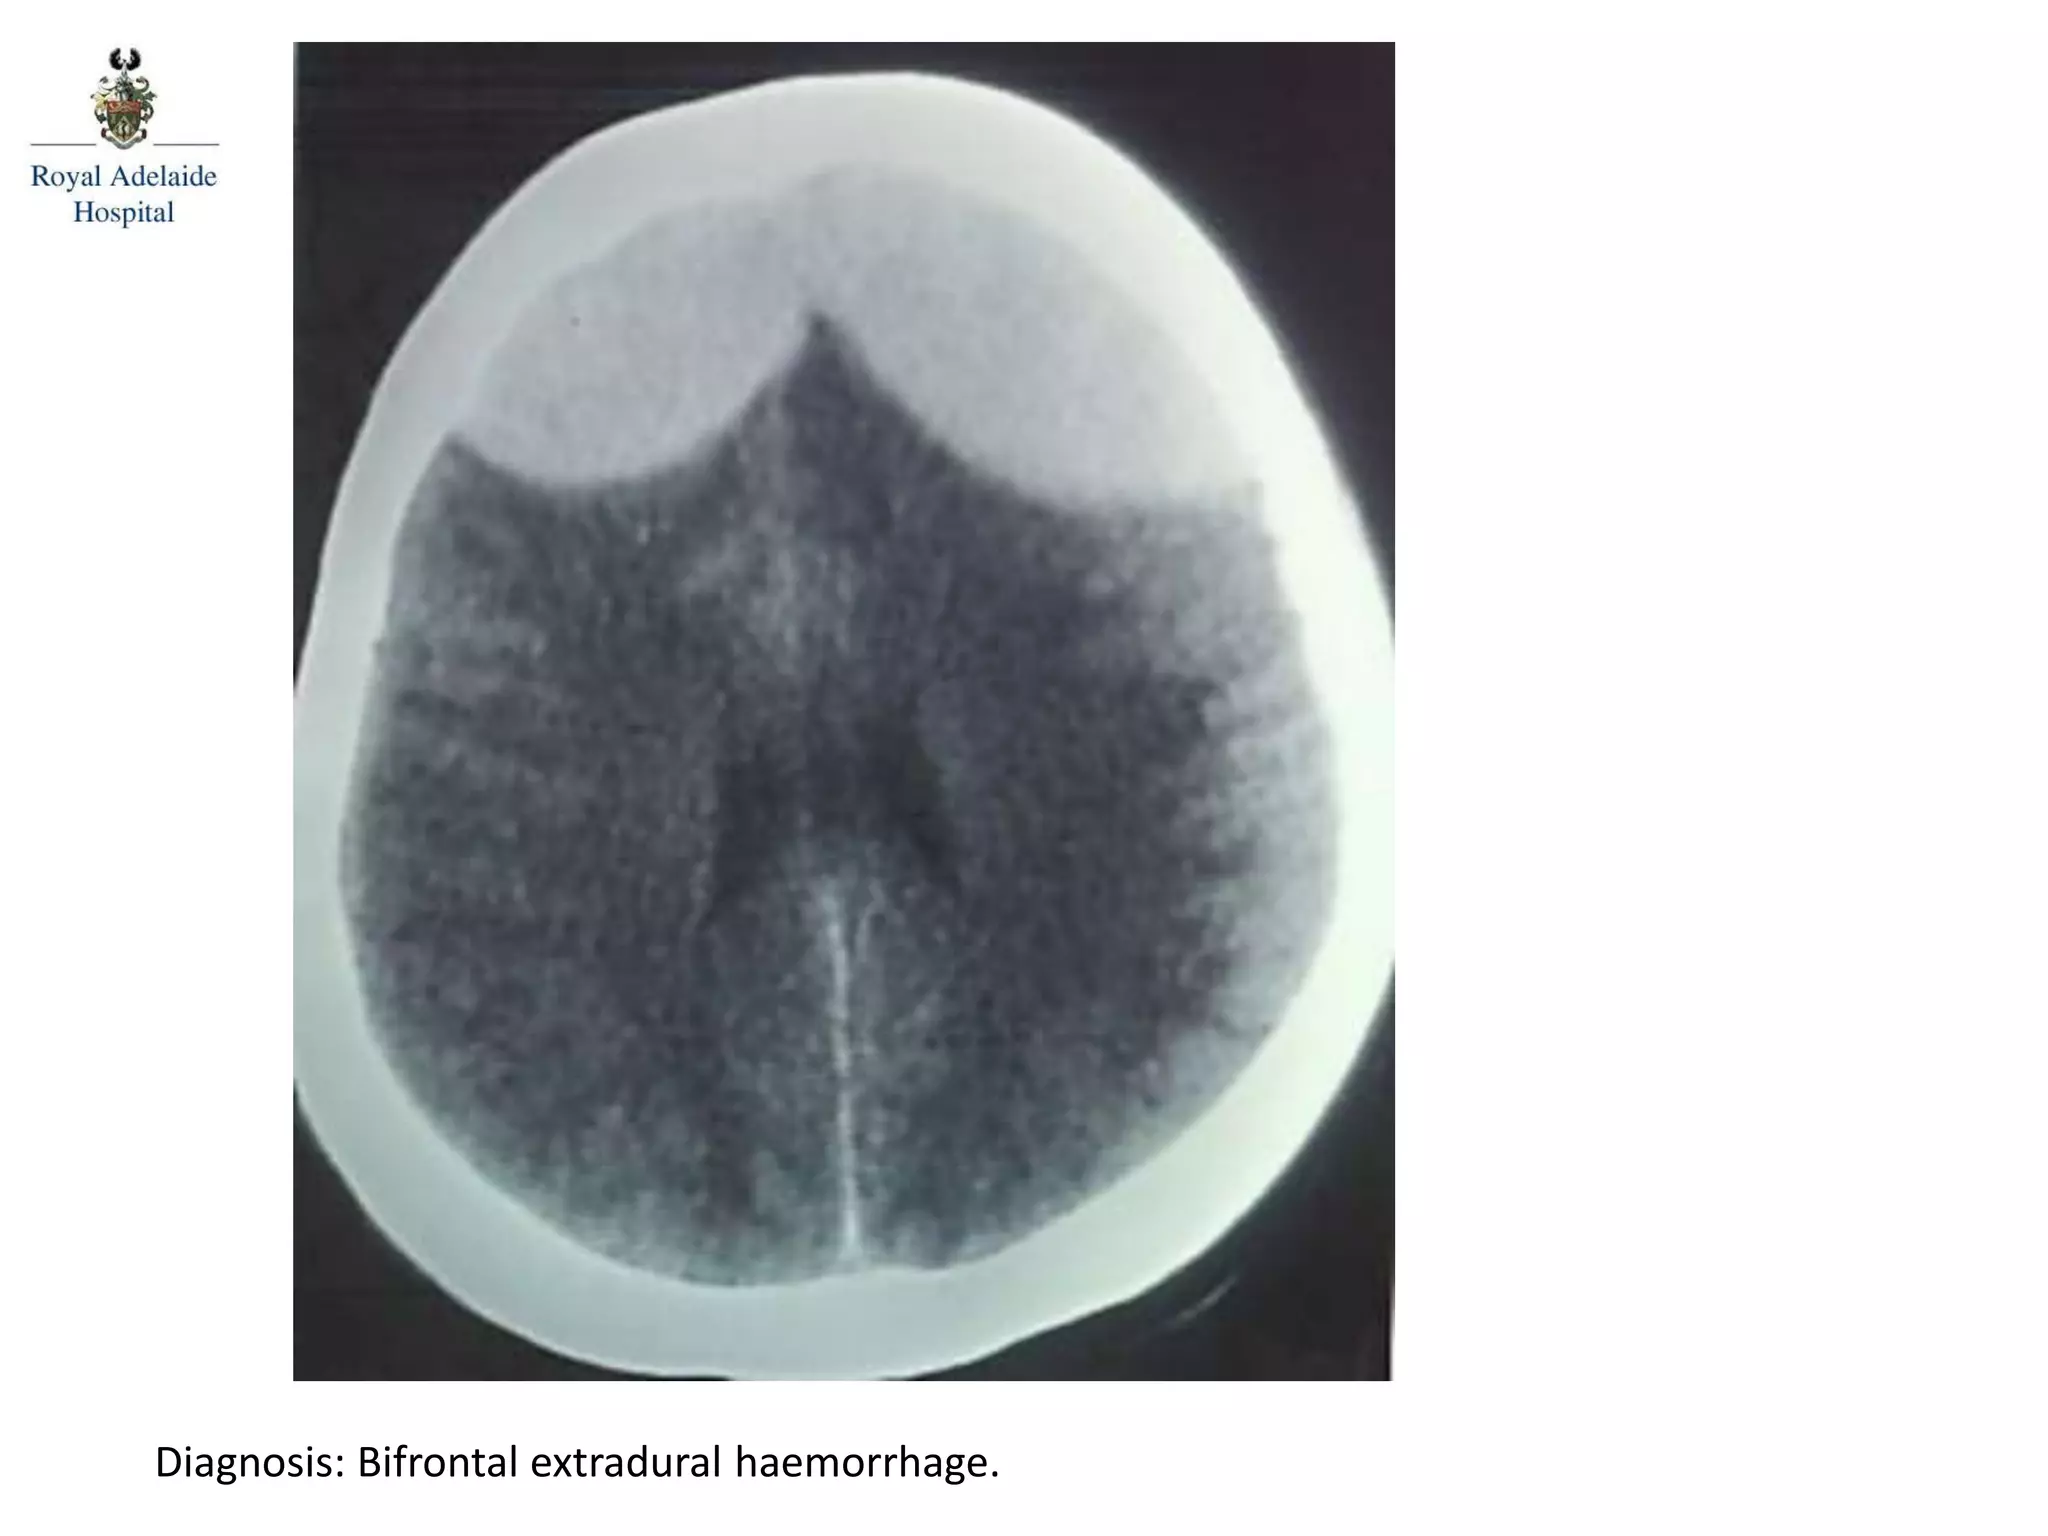

The document outlines multiple diagnoses from head CT cases, including small left basal ganglia bleed likely due to hypertension, various types of subdural and subarachnoid hemorrhages, and evidence of hydrocephalus. It details traumatic origins of some hemorrhages and notes obstructing masses and atrophic changes. Overall, there are significant findings indicating complications related to cerebral hemorrhages and ventricular enlargement.